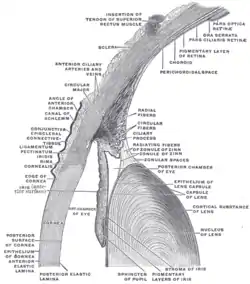

The lens capsule is a component of the globe of the eye.[1] It is a clear elastic basement membrane composed of collagen IV[2] laminin etc. [3][4] a quality that keeps it under constant tension.[5] As a result, the lens naturally tends towards a rounder or more globular configuration, a shape it must assume for the eye to focus at a near distance. The lens capsule is the thickest basement membrane in the body.[6]

Anatomy

The lens capsule is a transparent membrane that surrounds the entire lens. The capsule is thinnest at the posterior pole with approximate thickness of 3.5μm. Average thickness at the equator is 7μm.[5][9] Anterior pole thickness increases with age from 11-15μm. The thickest portion is the annular region surrounding the anterior pole. This will also increases with age (from 13.5-16μm).[10] The ligaments suspending the lens form attachments in the equatorial area and more so just to the front and back of the equator.[11] There are tens of thousands of these ligaments in a mouse lens and for the most part they appear to connect directly to the lens capsule.[12]

The structures in the images are consistent with the laying down of new capsular material required for growth. Even though the capsule is a highly elastic structure,[14] it contains no elastic fibers. Elasticity is because of the thick lamellar arrangement of the collagen fibers.[10]

The capsule helps give the lens its more spherical shape in aquatic vertebrates such as fish and more ellipsoidal shape in land based vertebrates such as sheep. In humans the lens ellipsoid becomes more flattened with age.[15] The capsule is the basement membrane for the epithelial cells at the front of the lens and the rapidly growing more flexible fiber cells of the back of the lens and below the epithelium at the front. Without the capsule substrate forming a tense support these cells lose their form as in the picture of a decapsulated sheep lens.

Normally, when ciliary muscles are in a relaxed state, the zonules will pull the capsule. Due to this zonular tension anterior lens surface is flatter resulting in more distant objects being in focus. When ciliary muscles contract, the zonular tension will reduce allowing lens to assume more spherical shape. This shape change increases the focusing power of the eye allowing closer objects to come into focus. The process of changing the lens's focusing power to see closer objects more clearly is known as accommodation.